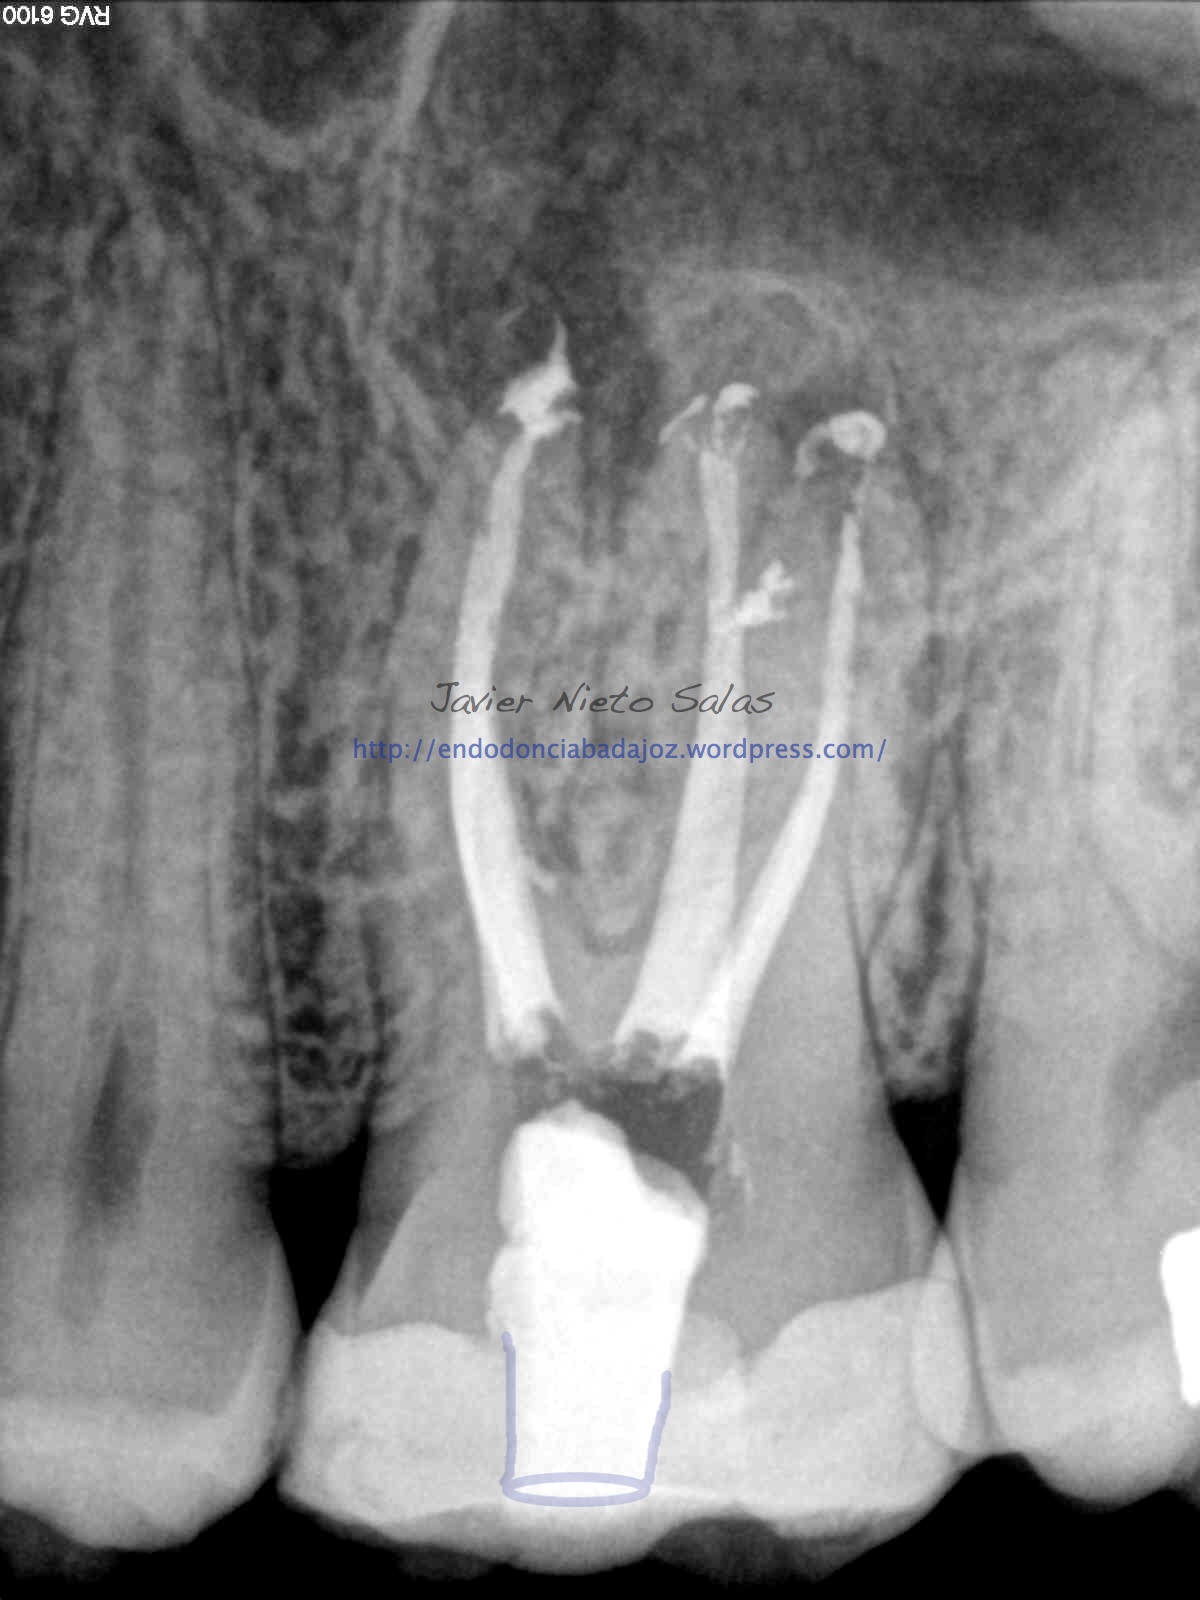

Nos llega un paciente con una PERIODONTITIS APICAL CRÓNICA, le realizamos el tratamiento de conductos, instrumentaríamos con sistema M-Two y obturaríamos con la técnica de Ola contínua de Buchanan y un backfilling con la pistola Obtura II. Se utilizó Microscopio Zeiss con luz xenón, y se han tomado las fotografías con una cámara Sony.

Como podemos ver, en las Rx finales, no afecta el ser conservadores con la estructura dentaria en el tratamiento y resultado final.